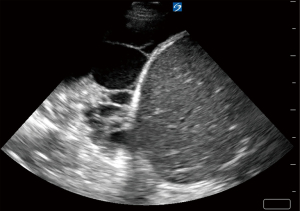

Parapneumonic effusions are categorized into three loosely defined stages: (I) simple or uncomplicated parapneumonic/exudative (stage I); (II) CPE/empyema/fibrinopurulent (stage II); and (III) organizing (stage III) (6). These stages exist along a continuum of an evolving process. An uncomplicated parapneumonic effusion refers to free-flowing effusions that are sterile. On pleural ultrasound, these effusions appear anechoic and lack complexity (7). A CPE refers to an effusion that has been infected with bacteria or other micro-organisms with a pleural fluid analysis demonstrating intense pleural space inflammation and/or positive gram stain. Pleural ultrasound will typically show septations demonstrating complexity in the pleural space (7). An empyema refers to a collection of pus. Pleural ultrasound for empyema may show a homogenously complex pleural effusion or complex septated (7) (Figure 1A,1B).

Thoracic ultrasound (TUS) has become ubiquitous in many ICUs and has the unique capability to identify a pleural effusion. In turn, this can aid with prediction of CPE and establish prognosis (7,11). TUS can facilitate timely administration of help in initiating early therapy, such as intrapleural fibrinolytics (12-14) (Figure 1A,1B). While computed tomography (CT) can diagnose underlying pneumonia, it is less useful in characterizing septations and other pleural space pathology or help to plan for safe entry into the pleural space. The transportation of unstable, critically ill patients may not be justifiable for the information obtained. CT scan has a role in patients who are not responding to therapy to identify alternate diagnosis or loculated pleural space not seen by TUS, such as fluid accumulation posterior to the scapulae or a mediastinal pocket.